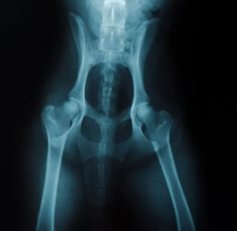

4) 진단 방법

보통 동물병원에서는 엑스레이(X-ray), 초음파, MRI 등을 통해 관절 구조를 확인합니다. 특히 전신마취 후 촬영하는 방사선 사진이 확진에 많이 활용됩니다.

초기에는 증상이 경미해서 보호자가 놓치기 쉽지만, 조기 진단이 곧 치료의 핵심이 됩니다.